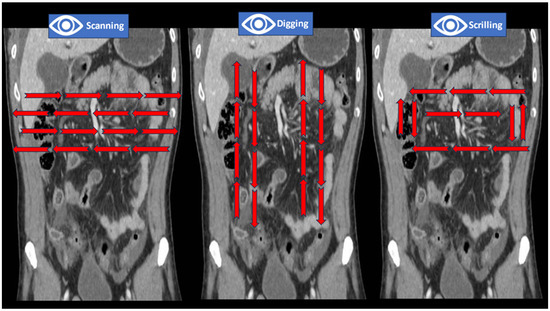

Contrast-enhanced CT implies the acquisition of images after the administration of oral or/and IV contrast. Although the administration of oral contrast is debatable, and no consensus on its use has been reached, IV contrast is recommended for most abdominopelvic acute conditions [31,32,33]. Without mentioning the subtleties and subphases of contrast administration, there are, in general, three moments for image acquisition that should be reviewed by the clinician: the arterial phase, the venous phase, and the delayed phase. All these are dynamic representations of tissular perfusion and urine excretion. During the first 40 s, the contrast enhances the arteries and well-vascularized structures; during the venous phase, paucivascular areas become visible, and during the delayed phase, kidney excretion and urinary structures are enhanced. Although surgeons do not devise examination protocols, they must recognize the three main phases—the arterial, venous, and delayed phases—of a contrast-enhanced scan, their utility in delineating anatomical structures, and the use of examination windows for grayscale adjustments (Figure 5).

Figure 5.

The ABC of lesion enhancement during CT interpretation ((A) attenuation, (B) best window, (C) contrast phases).

We grouped these instruments for image modulation under the practical name of “the ABC of lesion enhancements”, and we believe that, together with anatomical concepts and the use of clinical patterns, these form a triad for the correct interpretation of CT images by non-radiologists. Clinicians use a mental catalog of normal and abnormal findings when searching for lesions; hence, the following 16 steps should be approached in order during interpretation (Table 1, Figure 6).